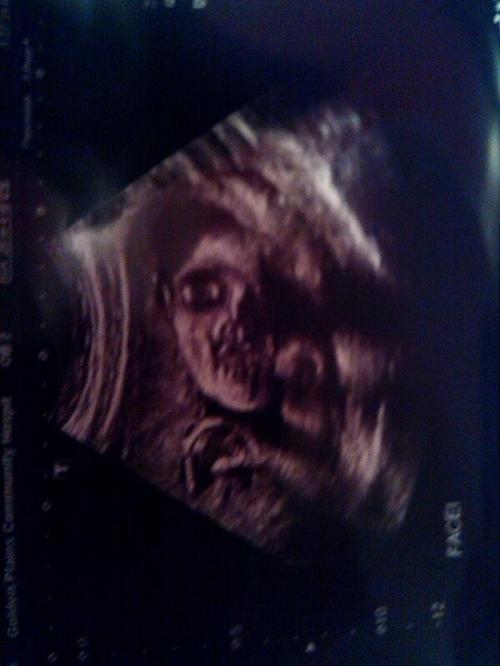

Снимок УЗИ

Реальное фото с ультразвукового исследования, сделанного в 1991 году.